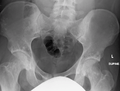

Osteopoikilosis of the hips on CT.